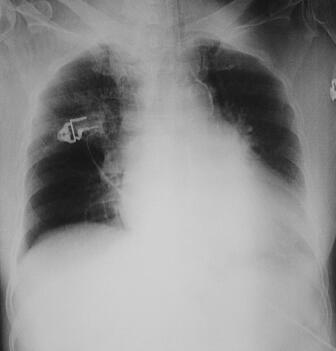

诊治经过:入院时给予美罗培南和莫西沙星联合抗感染、补液、纠正电解质紊乱等治疗措施。入院当天夜间患者HR 150~170次/分、BP降至90/50mmHg、SPO2降至93%,下颌式呼吸,胸腹皮疹增多,尿量开始减少。呼吸浅弱,给予气管插管、呼吸机辅助呼吸、多巴胺-多巴酚丁胺泵入、晶胶体液扩容、纠正酸中毒等治疗措施。血气分析示:pH 7.17,PCO2 42mmHg,BE −13.5mmol/L;凝血时间:PT 26.2秒,APTT 64秒,INR 2.06,纤维蛋白原2.78g/L。复查血常规:WBC 30.2×109/L,N 88%,PLT 164×109/L;尿常规:潜血(+),蛋白质(+),pH 5.0,比重1.025;复查胸片:心肺膈仍未见明显异常。入院后第2日将抗生素改为美罗培南和替考拉宁,继续扩容、纠正休克。分析昏迷原因可能有:①神经系统疾病感染;②休克;③服用了影响意识状态的毒物;④其他代谢性原因等。毒物分析:血中未检出毒物,排除中毒引起的昏迷。请神经内科会诊,考虑不排除化脓性脑炎,患者家属不同意做腰穿等检查操作,尿、便细菌培养为阴性。经中心静脉内扩容后患者心率有所下降,血压升至130/60mmHg,但仍昏迷。血生化结果:ALB 20.1g/L,ALT 72IU/L,AST 204IU/L,HBDH 342IU/L,Ca2+ 1.72mmol/L,BUN 11.14mmol/L,Cr 143μmol/L,LDH 745IU/L,CK 654IU/L,CK-MB 65IU/L。仍无尿,行床旁CRRT,当日APACHE Ⅱ评分为41分。入院后第3日患者应用冰毯下T 36.1℃,HR 130次/分,R 26次/分左右(呼吸机辅助SIMV),昏迷,疼痛刺激存在,出血点及小片瘀斑无明显增多。结膜水肿明显,口唇轻度发绀,双下肺呼吸音稍低,心律规整,未闻及杂音,肠鸣音弱,双下肢无水肿。双侧巴氏征(+)。3日内血常规:WBC 30.2×109/L→23×109/L→32.5×109/L,PLT 193×109/L→164×109/L→42×109/L;D-二聚体7817μg/L;PT 129.9秒;cTnI 1.5ng/ml。腹部B超:右肾囊肿,胆囊内膜欠光滑,胰、肝、脾、左肾未见明显异常,膀胱探查不满意。胸片:右上肺感染,左心室增大(图3)。入院后第4日仍用血管活性药维持血压,BP 110/60mmHg左右,出血点及瘀斑增多。复查血常规示:WBC 23×109/L,N 94.2%,PLT 18×109/L。血、尿培养未见细菌。给予静点血小板、少量肠外营养支持。入院后第5日患者外周血培养结果、病毒血清学检测结果均为阴性。请外院会诊,考虑诊断为中毒性休克综合征(TSS),主要为金黄色葡萄球菌外毒素作用所致。遂将抗生素调为利奈唑胺和美罗培南,同时增强细胞及体液免疫、清除炎性介质及其他支持治疗。利奈唑胺前后共应用15天,美罗培南应用5天后降为头孢哌酮-舒巴坦钠。入院后第6日开始患者循环逐渐趋于稳定,血管活性药物逐渐减量,意识逐渐恢复,停呼吸机,拔除气管插管,全身状态逐渐改善。入院后2周患者病情平稳,无发热、咳嗽,无恶心、呕吐,腹痛、腹泻,鼻导管吸氧,SPO2 100%,循环稳定,大小便正常。查体无明显阳性表现,出血点及瘀斑大部分消退。CBC:WBC 11.5×109/L,N 74.1%,PLT 167×109/L。血生化全项大致正常。之后转至普通病房继续恢复性治疗。

图3 入院后第3日胸片